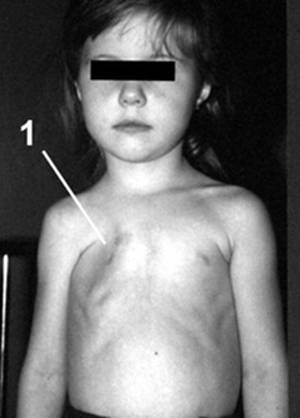

Рис. 1. Фото и рентгенограмма грудной клетки больной С. 4 лет с синдромом Поланда справа.

1 - гипоплазия 3 и 4 ребер справа.